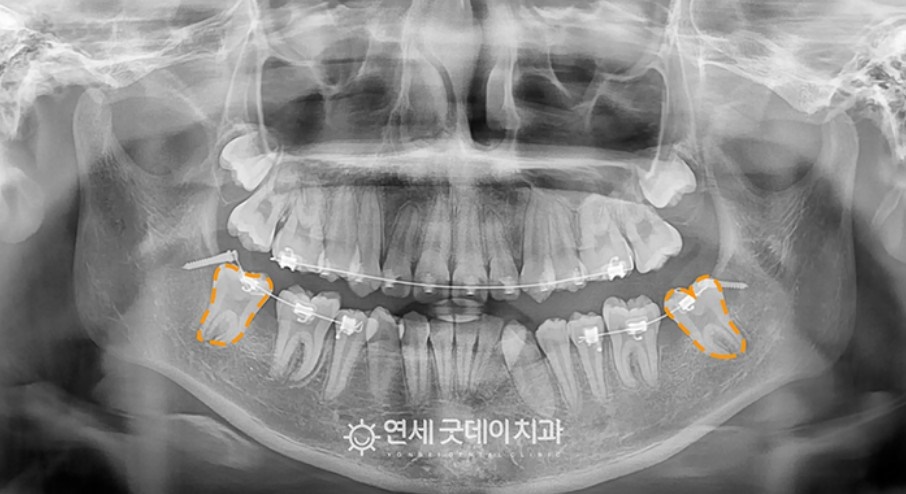

위 사진을 살피면 점차 치아가 서기 시작하는 것을 볼 수 있고, 마지막에는 교정치료를 적용해 자연스러운 치열을 얻을 수 있었습니다.

난이도가 높은 케이스였지만 간단한 국소마취 하에 30분 가량의 수술 시간으로 깔끔하게 치료해 드렸습니다. 결과적으로 틀어져 있던 위 덧니는 짧은 시간 내에 가지런해지고, 웃을 때도 치아 배열이 고르게 바로 잡혔습니다.